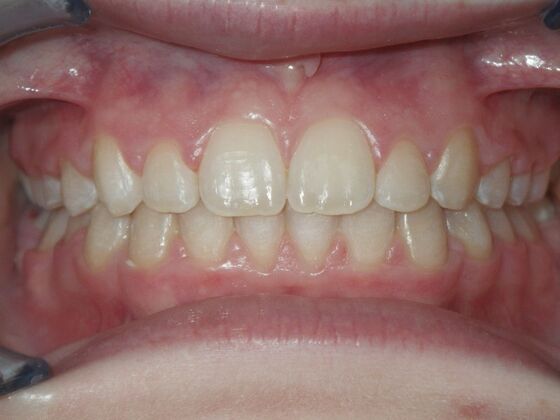

Patient is 9 years old and presents with 100% overbite and blocked out upper and lower lateral incisors. Both upper central incisors are palatally inclined causing a lack of space available for most anterior teeth. Advised her parents that she needs Phase I Interceptive Orthodontic treatment to provide room for all upper and lower front teeth. Phase I treatment was begun and finished, then began Phase II treatment shortly thereafter to finalize case. Removable retainer were fabricated for retention.